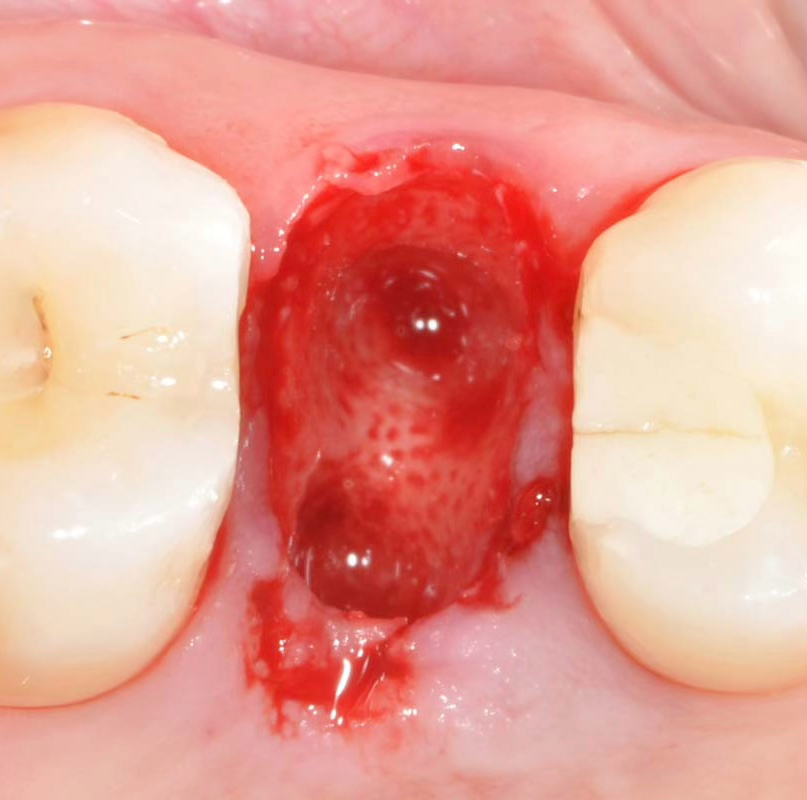

1단계: 발치 후 소켓

치아 발치 후 비어있는 발치소켓

2단계: 실제 발치부

발치 후 넓은 빈공간이 보이는 실제 임상